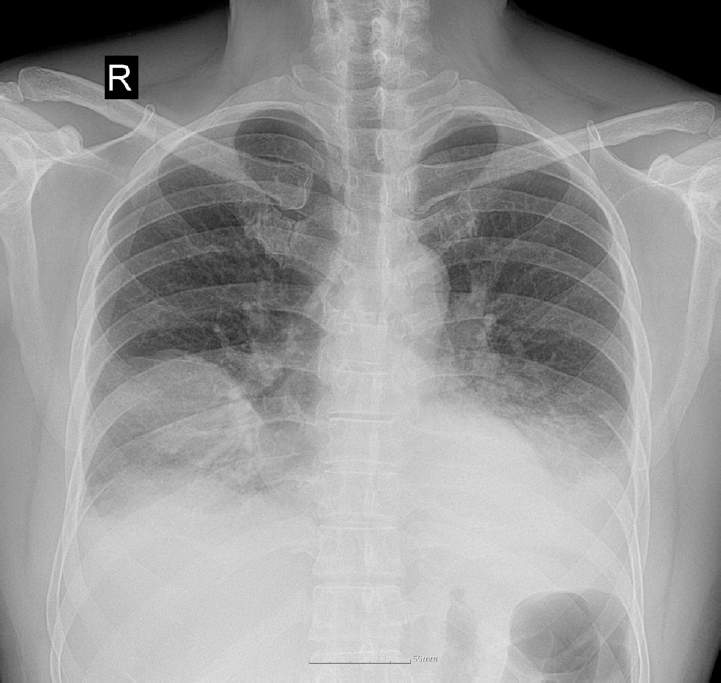

Upon admission, his vital signs were as follows: blood pressure, 100/60 mmHg; pulse rate, 120 beats/min; respiratory rate, 20 breaths/min; and body temperature, 38.2°C. Pulse oximetry revealed that oxygen saturation was 95% on room air. Chest auscultation revealed crackling rales in the lower bibasilar lobes. Initial laboratory investigations showed significant leukocytosis with white blood cell (WBC) count of 28,100 cells/µL and elevated C-reactive protein (CRP) level of 35.39 mg/dL. To evaluate for potential secondary infection, multiple microbiological cultures were performed during the early hospital course. These included blood and sputum cultures on the day of hospital admission (day 1), a follow-up sputum culture on day 2, and sputum and urine cultures on day 3. All cultures yielded no specific growth. Chest radiography revealed bilateral pleural effusions and patchy consolidations in both lower lung fields suggestive of pneumonia (Fig. 1). Contrast-enhanced computed tomography (CT) of the chest revealed ground-glass opacities in the right middle lobe, base of the right lower lobe, and left lower lobe, accompanied by intrinsic air and bronchovascular bundles. Based on these findings, the patient was admitted to the intensive care unit with a diagnosis of encapsulated necrotizing pneumonia.

Fig. 1.

Initial chest radiograph showing bilateral patchy consolidations over lower lung fields with pleural effusion.

Fig. 1. Initial chest radiograph showing bilateral patchy consolidations over lower lung fields with pleural effusion.